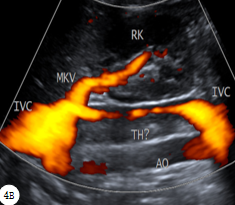

河北医科大学第二医院 东院区超声科 赵雅培患儿女,13岁,因“腰痛伴发热5天、呼吸困难3天”就诊。患儿于5天前无明显诱因出现腰痛,为持续性胀痛,伴发热,无心慌、乏力,无尿频、尿急,于3天前就诊于当地县医院。腰椎正侧位示:腰椎骨质结构未见异常。超声检查:肾脏未见异常,下腔静脉血栓(图1)。肺部CT示:双肺片状渗出(肺炎)。遂行经颈静脉穿刺置管溶栓术、抗感染,患者症状未改善,为进一步诊治遂入我院。急查超声并完善各种检查,下腔静脉超声:①下腔静脉溶栓导管(图2A)②下腔静脉肾静脉水平以下血栓伴管腔重度狭窄(较溶栓前范围明显延伸,图2B)。WBC 2.90×109/L,N 91.69%;CRP 191.8mg/L,FDP 91.81ng/L,D二聚体 7.6ug/ml。血培养:金黄色葡萄球菌阳性。考虑患儿“重症肺炎、脓毒症、下腔静脉血栓伴脓栓”诊断成立。考虑溶栓导管术后疾病进展,遂拔除颈静脉置管,静脉注射人免疫球蛋白支持治疗,中和免疫介质,调节免疫力。患儿住院第6天,体温较前升高,最高达38.8℃,间断诉胸闷、呼吸困难,伴烦躁,腰痛;WBC 15.08×109/L,N 93.42%;CRP 286.00mg/L,FDP 15.07ng/L,D二聚体 1.35ug/ml,抗凝治疗有效。肺部CT:两肺广泛多发团、片状结节,部分病变内见小空洞,考虑多发感染(图3A)。追问病史,患儿于1月前面部疖肿,累及范围较大、位置较深,有挤压史,迁延自愈,故金黄色葡萄球菌感染来源及诊断明确。患儿住院第16天,体温恢复正常,阵发性咳嗽伴右侧胸痛,偶诉腰痛。胸部螺旋CT:两肺内多发球形或团状病变及大部形成空洞或空腔,大部病变空洞内壁较为光滑,壁厚而不均匀;左肺气胸(图3B)。超声:下腔静脉肾静脉以下血栓伴重度狭窄(较入院时略有缩窄,图4A~B)。继续抗感染、抗凝治疗;发病第53天彩超:下腔静脉肾静脉水平以下附壁陈旧性血栓(较前明显缩小,图5);3个月彩超:下腔静脉血栓消失。 图1 溶栓前下腔静脉血栓 图2 A:下腔静脉溶栓导管;B:溶栓3天后下腔静脉血栓;图3 A:住院第6天两肺广泛多发团、片状结节,部分内见小空洞;B:住院第16天两肺多发球形或团状病变,大部形成空洞或空腔;左肺气胸 图4 住院第16天A:下腔静脉血栓;B:彩色多普勒能量图下腔静脉管腔内窄带状血流信号 图5 发病第53天下腔静脉后壁陈旧性血栓(IVC:下腔静脉,AO:腹主动脉,RK:右肾,TH:血栓,MKV:主肾静脉,RKV:右肾静脉)讨论 下腔静脉血栓(inferior vena cava thrombosis,IVCT)是一种比较严重且危急的疾病,可导致急性肺栓塞而危及患者生命[1]。众所周知:炎症和血栓不是相互独立的病理过程,一方面炎症促进血液高凝状态,易导致血栓形成;另一方面血栓形成中的物质也可引起炎症;二者相互作用、恶性循环。导管接触性溶栓(catheter-directed thrombolysis,CDT)是导管置于血栓内部,增加溶栓药物与血栓的接触面积,全程作用于血栓内部,增加局部药物浓度,提高溶栓效率,避免短时大剂量应用溶栓药物带来的出血等风险,使溶栓效果更确切、安全有效[2]。本病例溶栓后血栓大面积延伸、脓毒血症发生,分析原因有二:一是溶栓前患儿已有感染症状、金葡菌阳性,白细胞低、免疫力低下;二是溶栓后,导管进入血栓内部,会导致血栓物质与炎症因子的进一步结合,加速血栓发展、形成严重的全身化脓性感染。另外,对于无明确伴发炎症的IVCT,进行CDT必须在置管过程保证严格无菌操作,以防出现导管内感染、脓毒症发生。脓毒症指由感染引起的全身炎症反应综合征,可由身体任何部位感染导致,如蜂窝织炎、脓肿、脑膜炎等,常出现明显肝功能受损[3];本患儿感染来源于面部疖肿既往史。WBC是重要的血细胞,具有吞噬异物的作用,可抵抗病原体入侵。吴青等指出WBC计数检测结果易受机体免疫、应激、疾病等多种非感染性因素影响,如免疫力低下的患儿细菌感染严重时WBC计数升高也不明显,对疾病状态无法正确评价[4]。该患儿初期WBC低于正常水平,后经正常至显著升高,与上述解释一致。下腔静脉内占位病变包括血栓、癌栓、肿瘤及假性病变等,以血栓最为常见。该患儿既往体健,结合病史可以明确下腔静脉血栓。血栓早期为急性、亚急性期,灰阶超声表现为极低回声或低回声,管径相应增宽;慢性期则表现为中等回声或钙化强回声,管径变细。彩色超声示血栓内无血流信号,与管壁分界不清[5]。该病例住院前县医院超声检查、住院后急诊床旁超声检查,灰阶模式声像图表现由团状高回声转归为长带状不均匀低-高回声(图1,2B),虽不影响血栓诊断,但受仪器条件限制管壁与管腔显示欠清晰。后两次检查均使用大型超声诊断仪采集声像图,血栓由带状等回声转归为带状高回声,管壁与管腔清晰度明显提高(图4A,5)。彩色多普勒能量图(CDE)是一种以能量模式显示的血流成像技术,具有更高的血流敏感性,尤其是显示流速较低的静脉边缘血流,血流充盈度更真实(图4B)。综上所述,超声医生在诊断中应该详细追问病史、结合实验室,明确诊断是单纯性血栓,还是血栓伴脓栓,为临床医生实施CDT治疗提供可靠依据。参考文献[1] 张志文,陈学明,冯海,李晨宇,于宏志,张忠涛.临时滤器联合经导管血栓抽吸术和导管接触性溶栓治疗下腔静脉血栓[J].中国血管外科杂志(电子),2020,12(3):222-226.DOI:10.3969/j.issn.1674-7429.2020.03.011[2] Wang L,Zhang C,Mu S,et al.Safety of catheter-directed thrombolysis for the treatmentof acute lower extremity deep vein thrombosis:a systematic review and meta-analysis[J]. Medicine, 2017, 96(35):e7922.DOI:10.1097/MD.0000000000007922.[3] 张韬,张丽娟,王红霞.脓毒症患者病原学特征、肝功能及sTREM-1水平分析[J].中国病原生物学杂志,2019,14(06):710-712.DOI:10.13350./j.cjpb.190619.[4] 吴青,柴建农,徐咏梅,等.常用检验指标在无明显感染灶幼儿急性发热诊断中的价值[J].临床儿科杂志,2015,33(05):454-458.DOI:10.3969j.issn.1000-3606.2015.05.014.[5] 宋奕宁,赵艺超,李建国.下腔静脉肿瘤的超声影像诊断与鉴别[J].中国超声医学杂志,2018,34(1):37-39.DOI:10.3969/j.issn.1002-0101.2018.01.012.